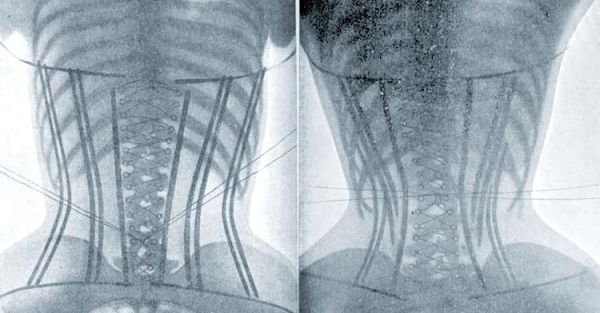

束腰带在市场上备受瞩目,尤其是微商们的热推。然而,这并非束腰的全新亮相,实际上,它在欧洲宫廷中早已有着悠久的历史。无论是东方还是西方,对于“柳腰”的审美标准始终如一。过去,束腰多采用皮质或布织材料,而如今,无论是美体还是健身用途的束腰,都离不开科技的助力,以弹力纤维混织为主。

束腰带真的健康吗?事实上,它可能给身体带来不小的隐患。由于束腰带紧箍腹部,过度紧绷的束腰会严重阻碍体内的血液循环。佩戴时间越长,束缚力度越大,这种压迫就愈发明显。长期佩戴过紧的束腰,不仅可能损害内脏,还可能引发一系列健康问题,如头晕、恶心等不适感。

此外,束腰还会直接压缩内脏的分布空间,进一步加剧对内脏的压迫,从而对身体健康造成潜在威胁。